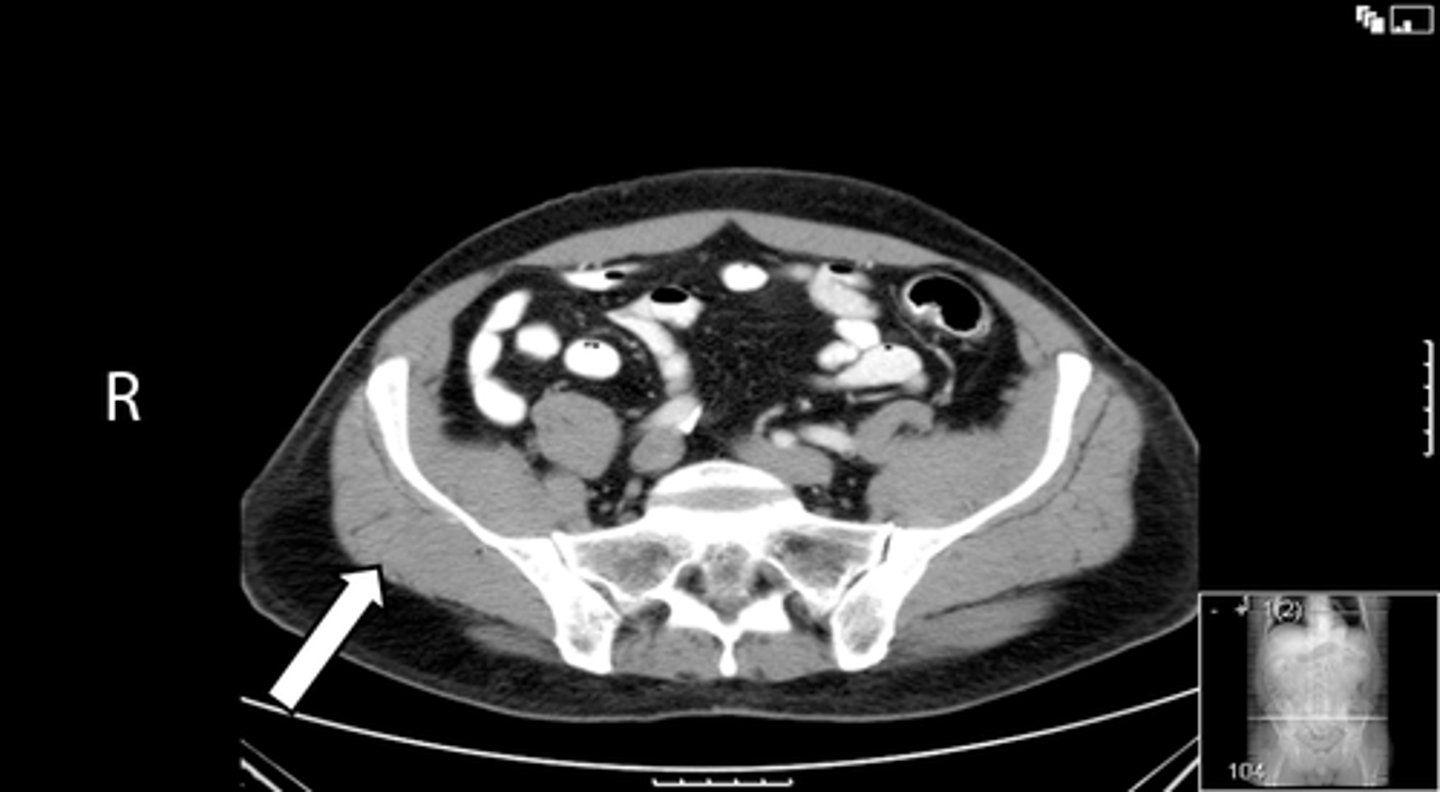

Axial bony pelvis CT

What is the image?

32

L ilium

What is indicated in the image?

<p>What is indicated in the image?</p>

33

New cards

L sacroiliac joint

34

R ilium

35

R sacroiliac joint

36

Sacrum